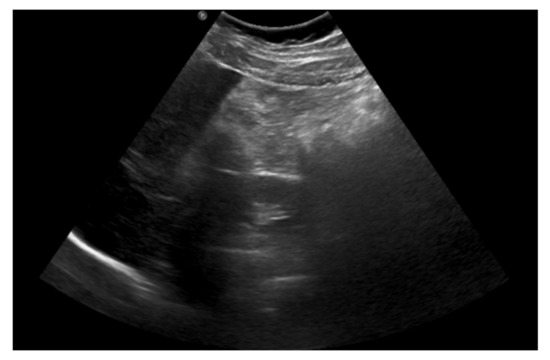

On admission, the patient presented with severe epigastric pain lasting for 3 days. In addition, the parents reported one episode of vomiting and stool retention lasting 2 days. The girl had no fever. On physical examination, the abdomen was distended. On palpation, significant pain, with increased tension of abdominal integuments in the right and central epigastrium, was observed. The lower quadrants of the abdomen were soft with mild tenderness, with palpable stool masses in the lower left iliac fossa. The percussion examination was impaired by the excess amount of subcutaneous tissue with tympanitic sounds in the epigastrium and slightly dull sounds over the left iliac region. Peristalsis was heard in the umbilical region. The pain intensified with changes in position. Diagnostics for acute abdominal diseases were implemented. The differential diagnosis included acute pancreatitis, gastrointestinal obstruction, gastrointestinal perforation (including duodenal perforation) and acute appendicitis. Laboratory tests showed elevated inflammatory parameters: CRP (C-reactive protein) at 69.42 mg/L, insignificant leukocytosis with a WBC (white blood cell count) of 10.65 thousand/μL, with a neutrophil predominance of 71%, and fibrinogen at 524.7 mg/dL; the serum amylase and lipase levels were within normal limits. As for imaging examinations, a plain abdominal X-ray was initially performed, which showed no signs of obstruction or perforation of the gastrointestinal tract but did show fecal masses in the ascending colon and rectum (Figure 1).

Figure 1. A plain X-ray of the abdominal cavity on admission: no signs of obstruction or perforation of the gastrointestinal tract and fecal masses in the large intestine.